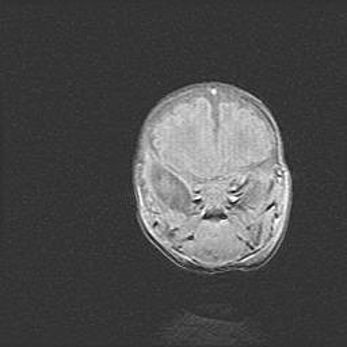

Открытая гидроцефалия.

Возраст: 9 месяцев 12 дней

Вес: 6800 г

Пол: мужской

Окружность головы: 41,5 см

Срок гестации: 28 недель

Гидроцефалия головного мозга у новорожденных имеет характерный признак: опережающий рост окружности головы приводит к визуально хорошо определяемой гидроцефальной форме сильно увеличенного в объёме черепа. Детские неврологи определяют следующие симптомы гидроцефалии у грудничков: выбухающий напряжённый родничок, частое запрокидывание головы, смещение глазных яблок к низу.